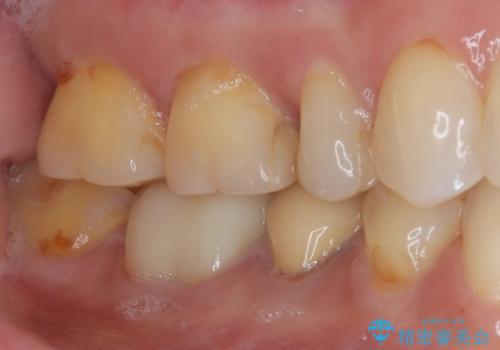

検診で見つかった齲蝕のセラミックインレー修復

- 検診で初期の齲蝕が見つかった患者様です。

これ以上神経の治療や被せものになりたくないため、初期のうちにしっかりとした治療をしたいとのことでした。

齲蝕をしっかりと除去して、精度の高いシリコーンによる型どりを行いセラミックインレーで修復しました。

唾液による接着阻害を防ぐために、ラバーダム防湿を行っています。